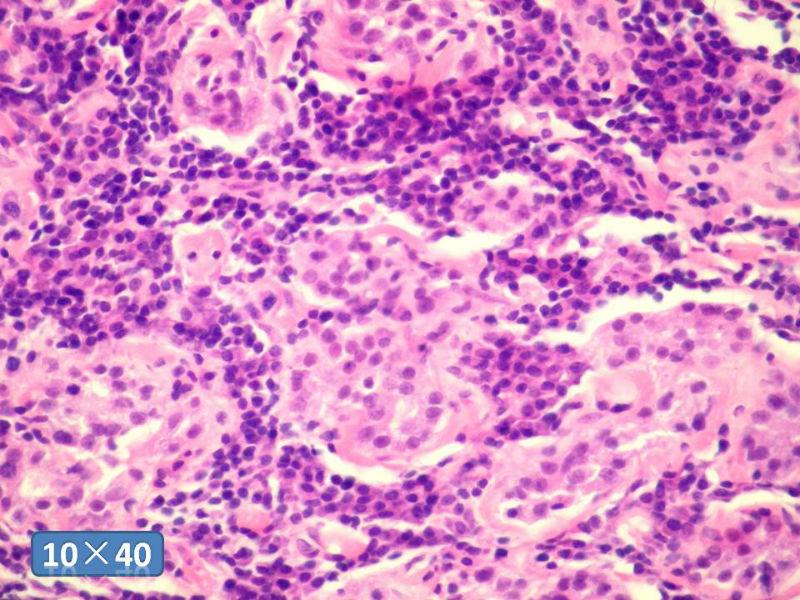

女性,50岁,乳腺肿物,冰冻切片(图1-25)

HE

DCIS LCIS IDC